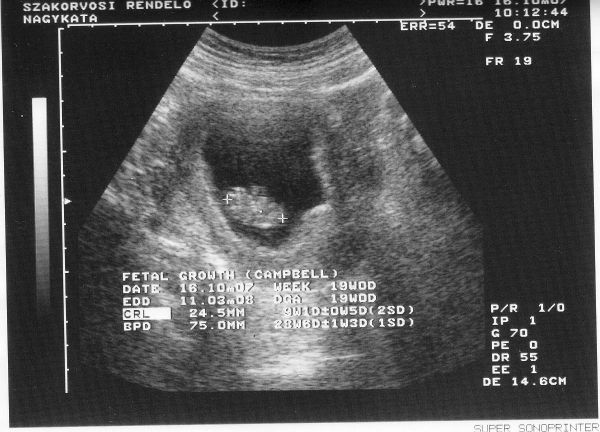

Vizsgálatokkal én még sehogysem állok, csütörtökökre tervezem az első labort. Bár én az áprilisiakhoz képest még ráérek. (Picit még mindig aggódom, hogy a 12. heti uh rendben legyen, annyi rosszat llehetett itt olvasni, ami elszomorította az embert. A doki pedig biztatott, hogy minden normálisnak tűnik.)